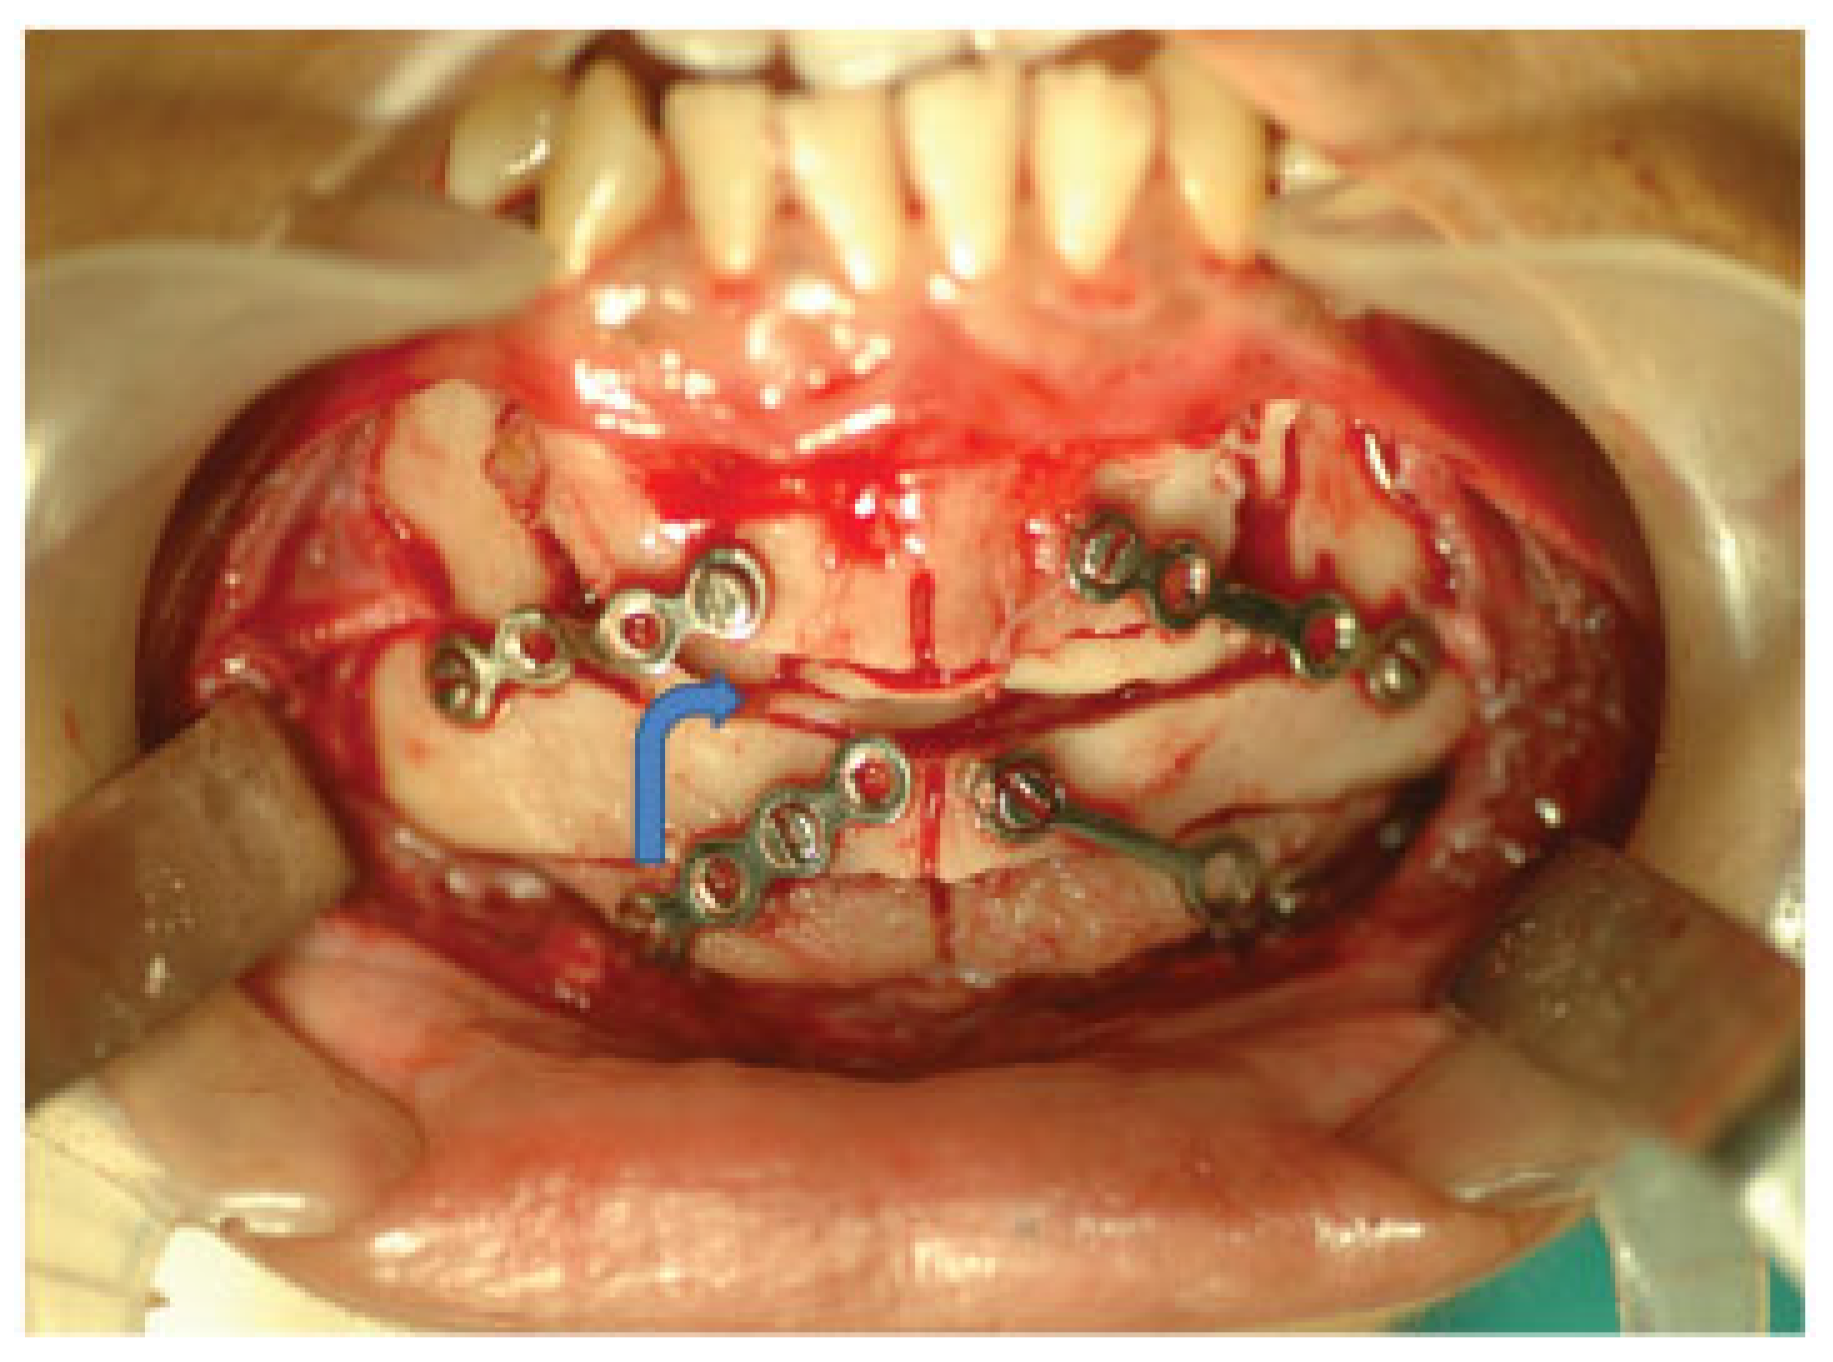

A Modified Kole's Osteotomy for Correction of Anterior Open Bite and Macrogenia in a Cleft Patient

:Surgical Method